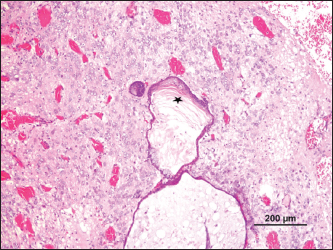

Fig. 5. Keratinized epithelium with an accumulation of laminated keratin (*), surrounded by well-differentiated nervous tissue (H&E).

Fig. 6. Ependymoma (H&E).

The mass presented areas of epidermal differentiation with laminated keratin and sebaceous glands. Cell differentiation into digestive and respiratory epithelium, bone, cartilage, and vast areas of differentiation into nervous tissue were also present (Figs. 37). Moreover, the nervous tissue presented focal areas of ependymoma. Epithelial areas with hypercellularity, cell atypia, stromal microinvasion, hemorrhages, and necrosis were also observed. Metastatic epithelial cells were detected invading the pancreas, the small intestine serosa, and the mesenterium. Therefore, the mass was classified as a malignant teratoma with abdominal carcinomatosis.